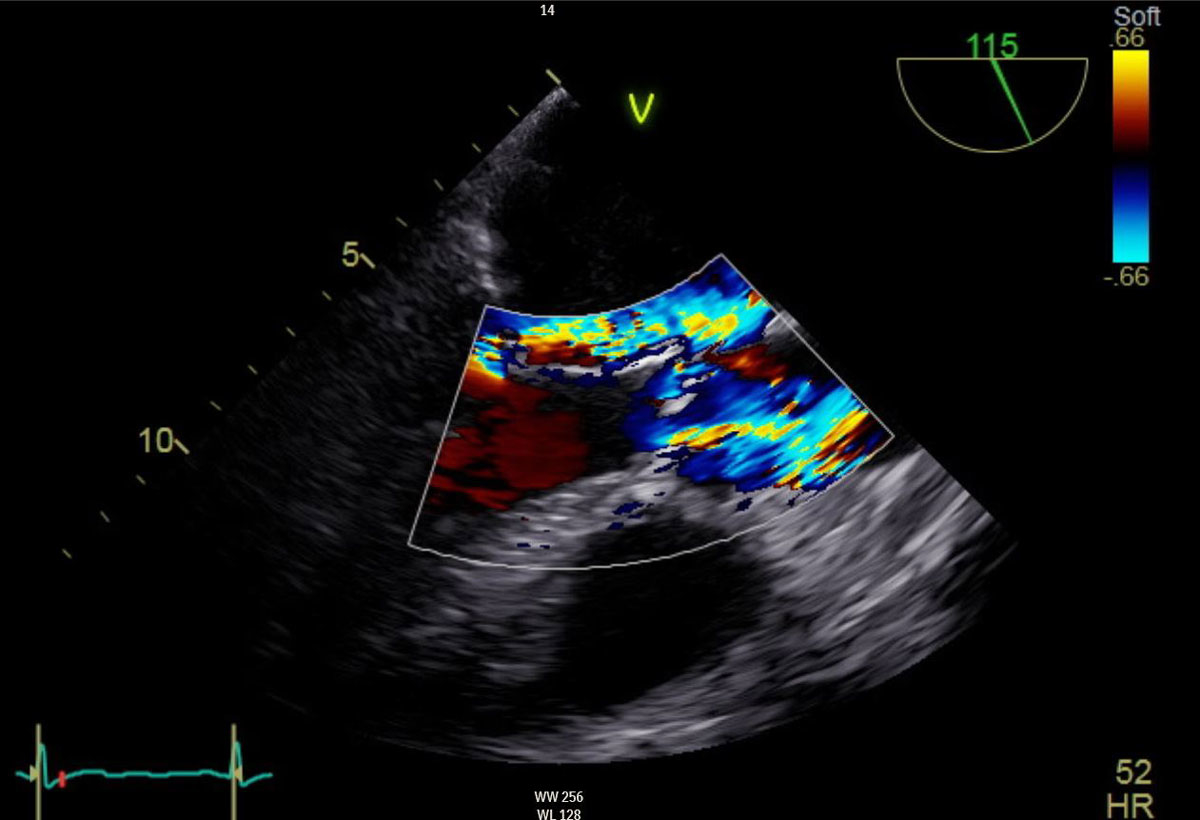

The 80-year-old female patient complained of dyspnoea on light exertion for almost a year, without orthopnoea or angina pectoris. After an episode of cardiac decompensation with pulmonary oedema requiring hospitalisation, the patient underwent an echocardiographic examination revealing severe mitral valve regurgitation because of rupture of tendinous cords with partial flail of the posterior mitral valve leaflet (fig. 1), as well as moderate aortic valve stenosis with a mean transvalvular gradient of 30 mm Hg on a tricuspid and severely calcified aortic valve. The left ventricular ejection fraction and dimensions were normal. Cardiac catheterisation showed no coronary artery disease and confirmed the above mentioned findings, showing an almost severe aortic valve stenosis with a mean transvalvular gradient of 36 mm Hg and with an indexed stroke volume of 42.6 ml/m2. Other comorbidities included chronic kidney disease (creatinine clearance 50 ml/min), status post invasive ductal carcinoma of the left breast with severe lymphoedema of the left arm, status post atrial flatter with conversion to sinus rhythm after treatment with amiodarone, arterial hypertension and severe obesity with a body mass index of 37.5 kg/m2. After interdisciplinary discussion in the heart team (cardiac surgery, cardiology and anaesthesiology) of our institution and because of the high calculated perioperative risk (EuroScore II 5.74%; STS score calculation not possible because of no support of combined mitral and aortic valve procedure) and frailty, it was decided to treat both valves concomitantly with a minimally invasive transcatheter procedure, through a left anterolateral thoracotomy, on a beating heart.

Figure 1 Severe mitral valve regurgitation with partial flail of the posterior mitral valve leaflet and moderate aortic valve stenosis. Preoperative transoesophageal echocardiography.